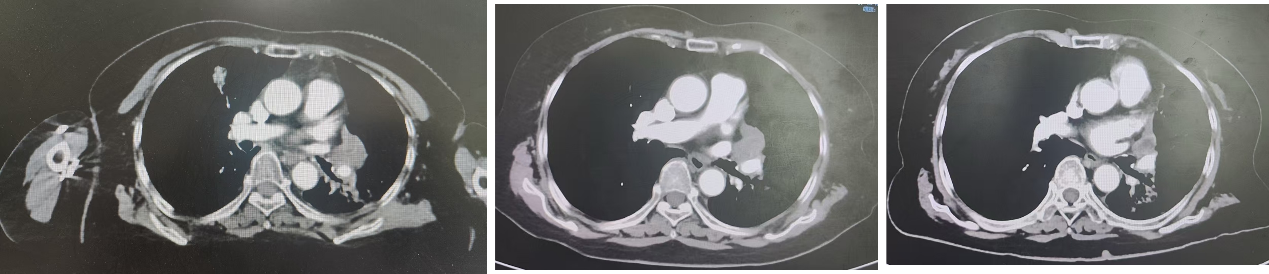

2023年4月17日入院完善相关辅助检查,行CT颈部平扫+增强扫描检查提示:1. 结合临床,左肺癌并阻塞性炎症及不张,左肺门及纵隔同侧淋巴结转移,较前(2023-1-28)好转;2. 左侧锁骨上小淋巴结,较前变化不著,建议观察。3. 肝囊肿,双肾囊肿,脂肪肝,肝内胆管轻度扩张。4. 甲状腺右侧叶低密度灶,考虑良性。5. 颅脑扫描未见异常。评价疗效部分缓解(PR),开始行斯鲁利单抗免疫治疗1周期。

治疗前胸部CT:

左肺癌,左肺门区结节,左肺上叶炎症,纵隔内及双肺门多发小淋巴结,请结合临床。

另左肺下叶小结节影,右肺上叶磨玻璃结节影,建议复查。双肺肺气肿、肺大泡。

治疗后1月胸部CT:

左肺癌,左肺门区结节,同2025年1月14日片对照较前缩小。纵隔内及双肺门多发小淋巴结,同前无著变。纵隔3A区低密度结节,较前缩小。

左肺上叶炎症,左肺下叶小结节影,右肺上叶磨玻璃结节影,建议复查,双肺肺气肿、肺大泡,同前无著变。

治疗后2月胸部CT:

左肺癌,左肺门区软组织影较厚,纵隔内及双肺门多发小淋巴结,同前2025年2月26日片无著变。纵隔3A区低密度结节,较前缩小。